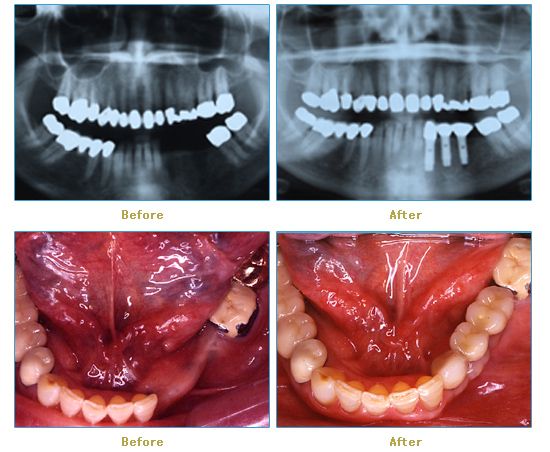

Dr. Cabianca has restored hundreds of smiles through the latest techniques in restorative and cosmetic dentistry. The following before and after photos document a few such cases in which Dr. Cabianca has replaced and reshaped teeth to produce wonderful smiles. Click on any of the images below to view larger versions of the photos.